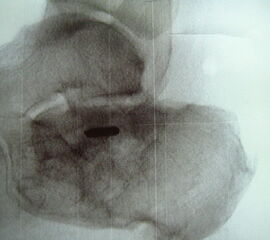

Knochenresektat sowie präoperatives CT (Sagittal- und Transversalebene) und intraoperative Bildwandlerkontrolle im seitlichen Strahlengang nach arthroskopischer Entfernung multipler Ossikel am dorsalen OSG/USG.

Große osteophytäre Anbauten, welche die FHL-Sehne vollständig ummauern, sind ebenfalls sehr gut in der beschriebenen Technik adressierbar. Präoperatives CT und intraoperative Bildwandlerkontrolle im seitlichen Strahlengang (linke Seite).